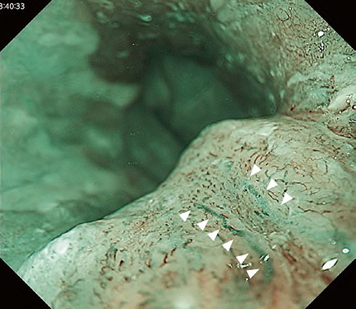

Predicting invasion depth of superficial esophageal squamous cell carcinoma is crucial in determining the precise indication for endoscopic resection (ER) because the rate of lymph node metastasis increases in proportion to the invasion depth of the carcinoma. Previous studies have shown a close relationship between microvascular patterns observed by magnifying endoscopy and invasion depth of the superficial carcinoma. Although there were two major classifications, Inoue and Arima, the Japan Esophageal Society (JES) integrated the two classifications and simplified it and developed a new magnifying endoscopic classification for the characterization and predicting invasion depth of superficial esophageal squamous cell carcinomas (SESCCs). This is essential for developing a treatment strategy for SESCC, in particular the indication for ER. Therefore, in this classification, morphological types of microvessels are classified into two categories of noncancerous [type A: normal epithelium, inflammation, and squamous intraepithelial neoplasia (SIN)] and cancerous (Type B: SCC) lesions. The cancerous types of microvessels corresponding to SESCCs are subclassified into three groups based upon an indication for ER as follows: an absolute indication type (Type B1: T1a-EP or T1a-LPM), a relative indication type [Type B2: T1a-MM or T1b-SM1(tumor invades the submucosa to a depth of 200 μm or less from the muscularis mucosa)], and a contraindication type [Type B3: T1b-SM2 (tumor invades the submucosa to a depth more than 200 μm)]. Diagnostic criteria of the JES classification are based on the degree of microvascular irregularity in the target lesion observed by magnifying endoscopy. Intrapapillary capillary loops (IPCL) are a basic unit of microvasculature in the stratified squamous epithelial layer. The microvascular irregularity is evaluated for the presence or absence of each of the following morphological factors: weaving (i.e., tortuosity), dilatation, irregular caliber, and different shape (i.e., various shapes). Microvessels are classified as type A if they have three or fewer factors (i.e., without severe abnormality; . Fig. 1a) and type B if they have all four (i.e., with severe abnormality). Type B is then subclassified into B1, B2, and B3 (. Fig. 1b–d, respectively) based on the running pattern or degree of dilatation of severely irregular microvessels. The definitions and schemas of type A and B vessels and predicted histology of invasion depth by type B vessels are summarized in . Table 1. A large scale validation study showed high overall accuracy (90.5%) of type B vessels of the JES classification. The most important auxiliary criterion in the JES classification is avascular area (AVA). AVA is defined as a low or no vascularity area surrounded by all subtypes of type B microvessels including B1 vessels. Diameters of AVA are positively correlated with sizes of histological cancer nest and the histological invasion depth of SESCC. Small (<0.5 mm), middle (0.5 ≤< 3 mm), and large (≤3 mm) AVA are suggestive of T1a-EP/ LPM, T1a-MM/T1b-SM1, and T1b-SM2, respectively. A key point to note is that any types of AVA (small, middle, and large) surrounded by B1 vessels are suggestive of T1a-EP or T1a-LPM SCC.